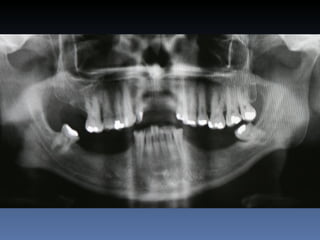

Dominga Maria silva

Idade – 53 anos

Sexo – Feminino

Raça – Caucasiana

ASA – II

Data- 23-04-2012

Diagnóstico:Desdentada parcial maxila

Plano de tratamento:      Reabilitação com 6 blocos

“onlay” provenientes de Úmero fresco-congelado

(FFB); reabertura para instalação de 6 implantes

dentários endo-ósseos e reabilitação protética fixa.

22-09-2011

20-04-2012

OPG Pré-op

Mensurações

Zona    Zona    Zona   Zona    Zona     Zona

1.6    1.3     1.1     2.1     2.3      2.6

Stage I       2,0mm   1,5mm 1,5mm 2,9mm 1,5mm         1,5mm

Pré-op (mm)

Stage I     6,5mm     7,0mm 7,1mm 5,2mm 6,7mm         7,0mm

Pós-op (mm)

Aument        4,5mm   5,5mm   5,6mm   2,3mm   5,2mm   5,5mm

o

Espessura

(mm)

Reabert       6,4mm   7,0mm   7,0mm 5,1mm     6,6mm   7,0mm

ura

Stage II

Reabsor       0,1mm   0,0mm   0,1mm   0,1mm   0,1mm   0,0mm

ção